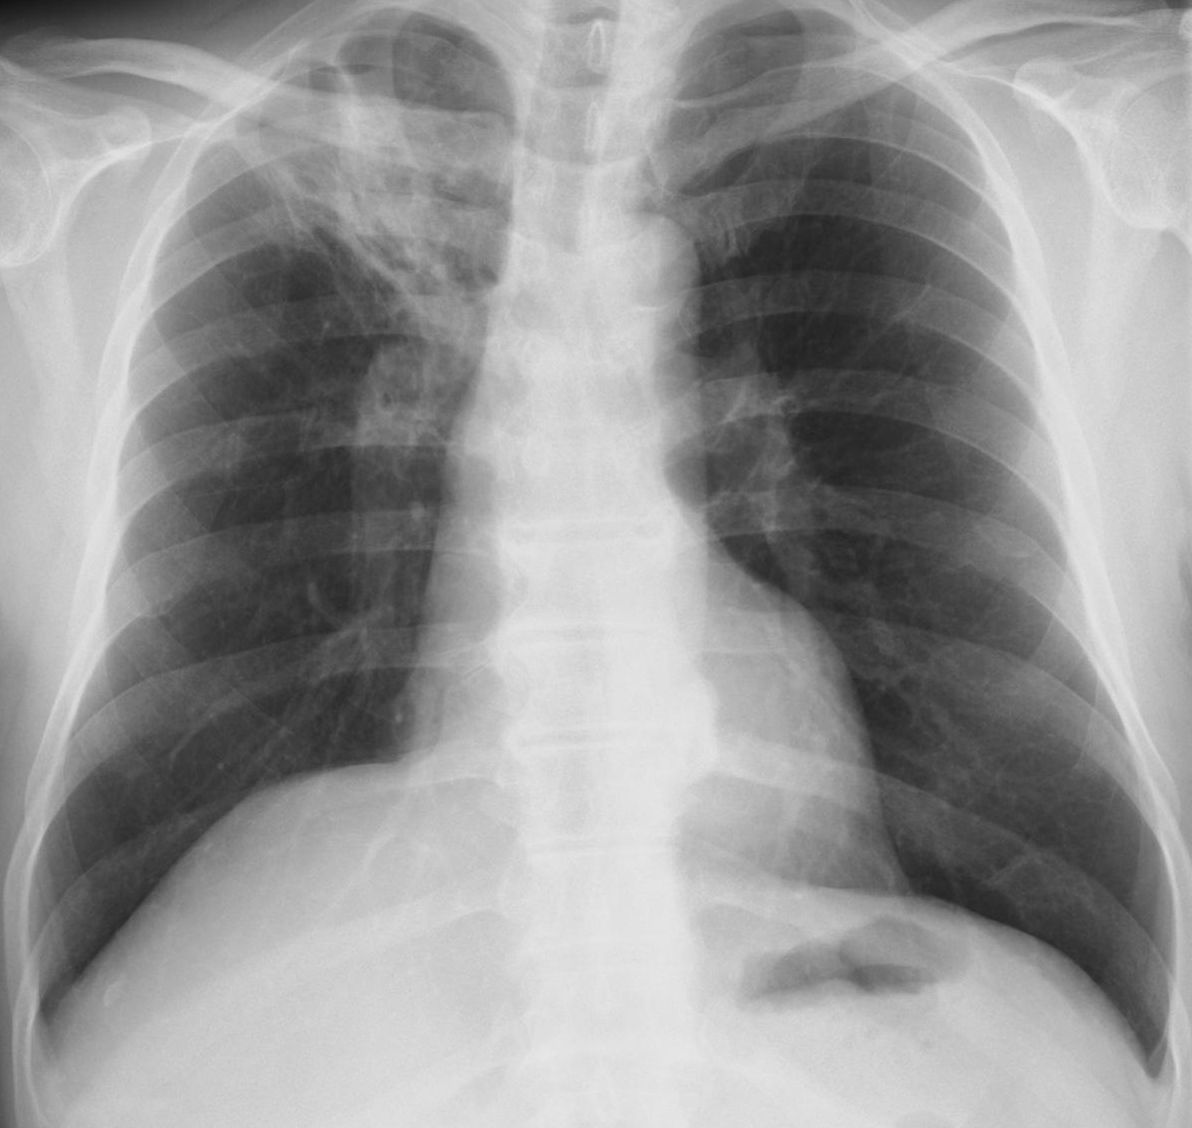

画像所見:来院時の胸部x線では、左上肺野に浸潤影を認めた(図1)。 図1 特発性器質化肺炎の患者さんの胸部x線画像 左上肺野に浸潤影が見られます( 青ライン )。. この ため感染から回復すると、炎症 部位の器質化は避けられず、気 腔、または肺胞腔内に肉芽組織 が出現する(器質化肺炎)。 気管支肺炎の画像所見として は、気管支周囲、あるいは細気 管支周囲の局所的な滲出(区域性分布)から、 1つ、または複数. 発行日 17年2月1日 Published Date 17/2/1.

特発性器質化肺炎の胸部ct画像 左の肺(写真の右側)に肺炎のような陰影がみられます 日本呼吸器学会では学会ホームページにて「のみなさま向」に様々なコンテンツを公開しています 。. 26 日本内科学会雑誌 第103巻 第11号・平成26年11月10日 Ⅱ.診断法の進歩 1.呼吸器感染症の画像診断 氏田万寿夫1) 佐藤 英夫 2)山口美沙子 要旨 市中肺炎でみられる画像パターンは気腔性肺炎と気管支肺炎パターンに大別され,肺野末梢の非区域性. Dec 5, 18 第48回城南・早良・西区胸部画像勉強会 ~器質化肺炎とは~.